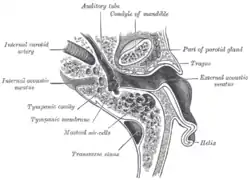

The sinuses at the base of the skull Horizontal section through left ear; upper half of section

Horizontal section through left ear; upper half of section Relations of the brain and middle meningeal artery to the surface of the skull